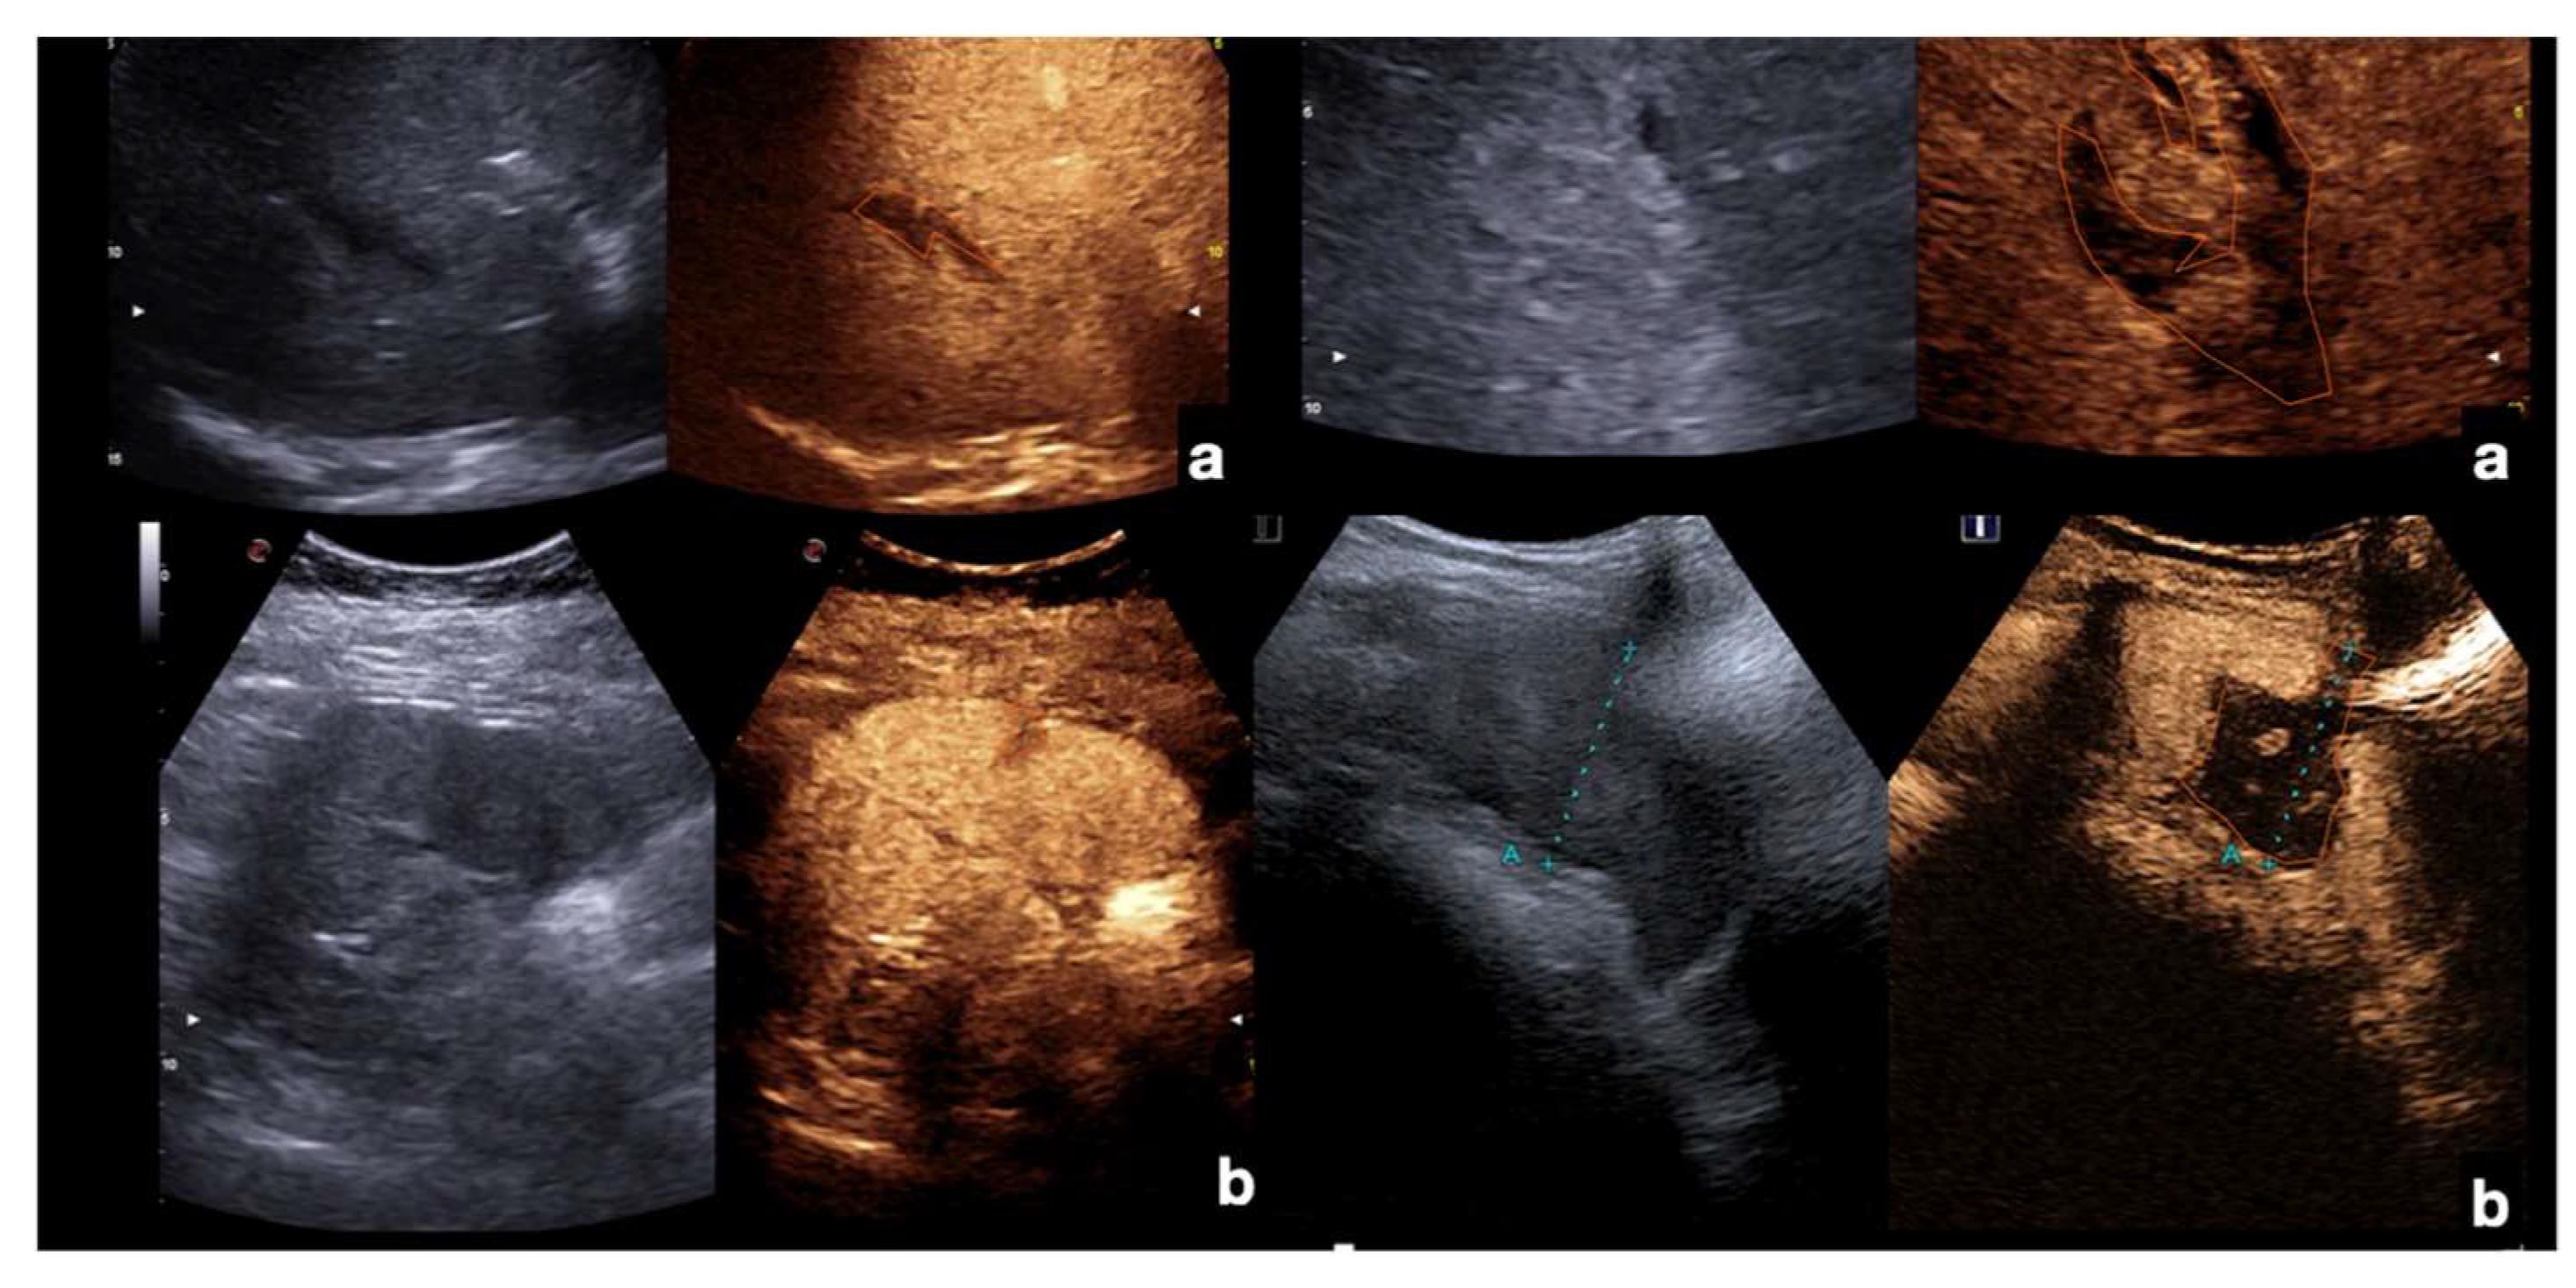

Lacerations: these findings are identifiable as irregular linear or branched non-enhancing bands, frequently perpendicular to the organ capsule, and can be associated with capsular discontinuity. Lacerations can be classified as superficial (≤3 cm in depth) or deep (>3 cm in depth) (Figure 12, Figure 13, Figure 14, Figure 15 and Figure 16) [13].

Figure 12.

Example of CEUS imaging of low grade (first column) and high grade (second column) injuries in the liver (a) and spleen (b) after moderate energy blunt trauma. Orange lines indicate parenchymal lacerations/haematomas.

Figure 15.

Admission CT (a,c,e) and follow-up CEUS (b,d,f) of the spleen in a 35−year-old patient after a fall from height. Follow-up CEUS was performed seven days after the CT. Note at CEUS the progressive enhancement, at different time points, of the healthy spleen parenchyma in venous phase, clearly demarcated from the subcapsular hematomas (b, orange line), from the contusion of the inferior-pole (d, orange line) and from a sub-capsular laceration (f, orange line). Adopted from ref. [30], 2021, Iacobellis, F.; et al.

Figure 16.

CEUS at day 1 (a) and after 2 weeks (b) in pancreatic trauma; note the reduction of the contusion area of pancreatic head, as well as of the peri-pancreatic fluid collection (orange line).